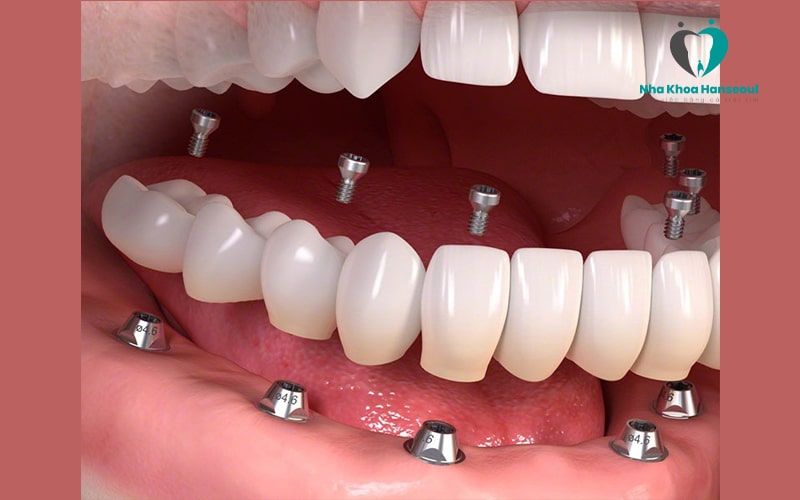

2.4 Implant All On 6

Implant All On 6 là giải pháp cải tiến hơn all on 4 khi sử dụng 6 trụ Implant để đặt vào xương hàm bệnh nhân. Với kỹ thuật All On 6, các trụ chân răng thường được dựng thẳng đứng. Vị trí lắp đặt cũng được phân bố đều khắp cả hàm.

Kỹ thuật này được sử dụng khi xương hàm của bệnh nhân mỏng hơn hoặc không đủ chắc chắn để sử dụng phương pháp implant all on 4.

Đây là 2 kiểu số lượng trụ chân răng phổ biến nhất. Ngoài ra còn có thêm các kiểu dùng 5 hoặc 8 trụ Titanium để phục hình.Tuy nhiên những phương pháp này ít được dùng hơn và chỉ sử dụng trong vài trường hợp nhất định.